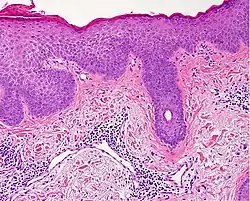

Spongiotic dermatitis

It is characterized by epithelial intercellular edema.[2]

| Generally/Not otherwise specified[notes 2] | Typical findings:[2]

Typical findings:[2]

PAS stain is essential to exclude fungal infection.[2] |

| Allergic/contact dermatitis or atopic dermatitis | As above. Eosinophils may be present in the dermis and epidermis (eosinophilic spongiosis).[2] | Allergic dermatitis

Atopic dermatitis

| Seborrheic dermatitis | Typical findings:[5]

Typical findings:[5]

In addition to above, an unspecific spongiotic dermatitis can be consistent with nummular dermatitis, dyshidrotic dermatitis, Id reaction, dermatophytosis, miliaria, Gianotti-Crosti syndrome and pityriasis rosea.[2][notes 2]